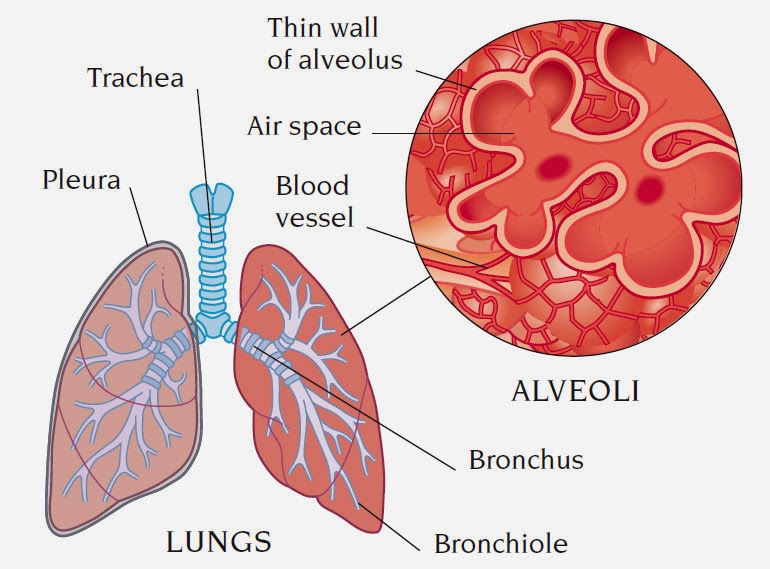

alveoli lung lungs gas exchange pulmonary anatomy alveolus membrane blood structure respiratory function microscopic supply infection disease

Lung anatomy & function. Alveoli bronchioles anatomy edu adapted. Organs and structures of the respiratory system